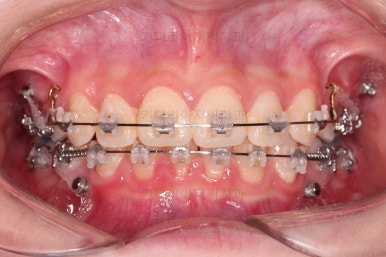

교합이 잘 맞아졌고요.

위아래 앞니도 서로 가까워졌어요.

치열도 가지런해졌고, 과개교합도 잘 개선이 되었습니다.

연산동치아교정 이제 전후 사진을 비교해 볼게요.

아래 앞니가 2개인 것이 표시가 안날 정도로 자연스럽게 교합이 맞아졌습니다.

얼굴모습에서도 발치교정이지 윗입술이 많이 들어가지 않게끔 아랫니를 최대한 앞으로 빼둔 상태여서 윗ㅇ입술은 양호하며, 아랫입술은 아래쪽에 깊게 패여있던 주름도 많이 퍼졌습니다.

여러 가지 제약이 많았던 상황이었지만 많은 부분들이 개선된 만족스러운 연산동치아교정 치료였습니다.

이상 아래 앞니가 2개 선천 결손인 환자분을 임플란트 없이 추가 발치로 교합을 맞춰주었던 연산동치아교정 치료사례였습니다.